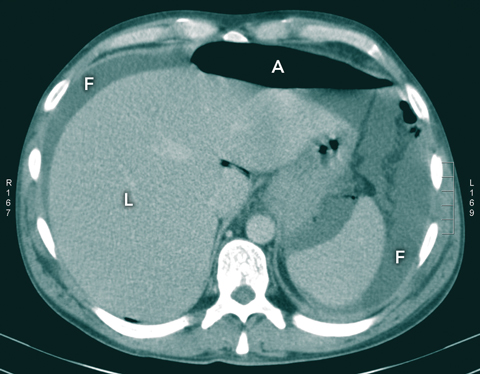

Intravenous contrast computed tomography revealed the presence of free fluid and gas in the peritoneal cavity (Box 2). An urgent laparotomy revealed a 1.5 cm gastric antrum ulcer with gross peritoneal contamination. Postoperatively, the patient was offered care at an inpatient drug and alcohol service, but absconded before transfer could be arranged.